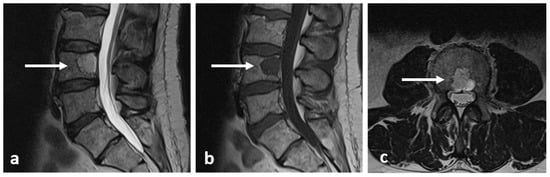

3.3. Osteoblastoma

| Osteoblastoma | Expansile lucent lesion. Sclerotic rim. Bone destruction. Variable intralesional ossification. | Low to intermediate T1 signal and intermediate to high T2 signal. Surrounding soft tissue oedema, extra osseous soft tissue component. |